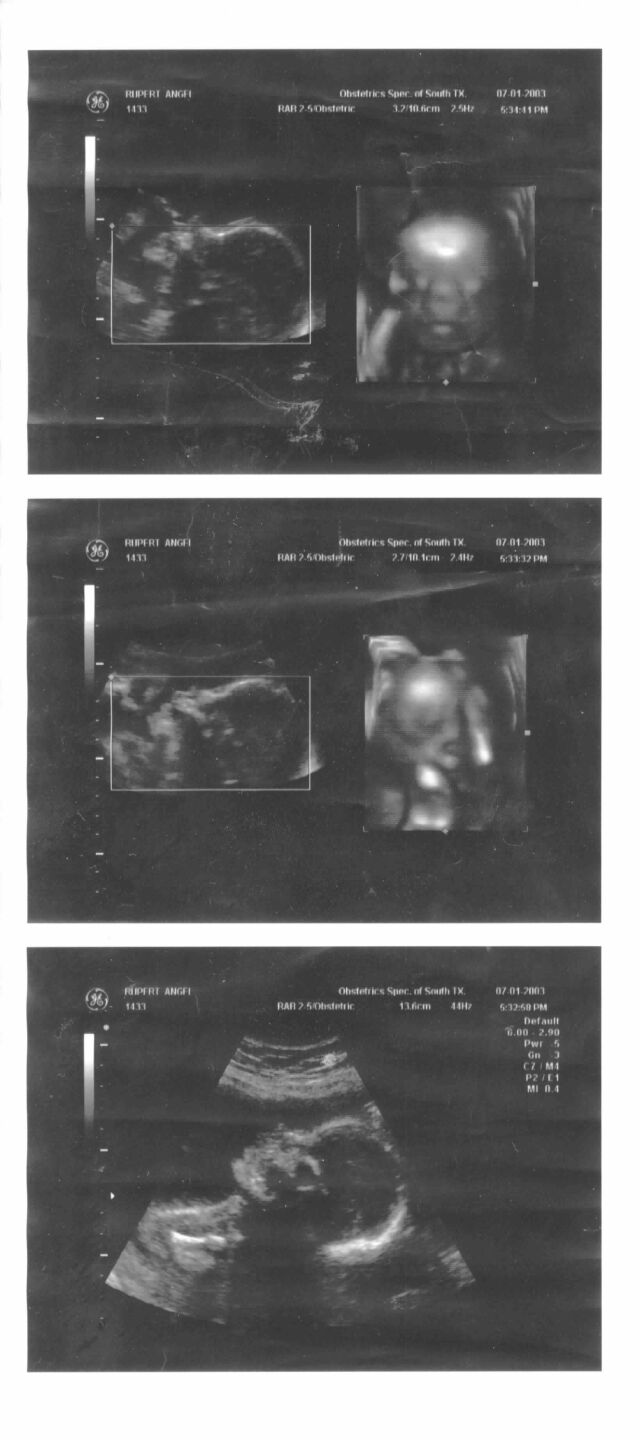

Savannah's Birth

This was the first year 3D ultrasonic imaging was available. All pictures taken with a Medion MD9721 4.1 MP Digital Camera.